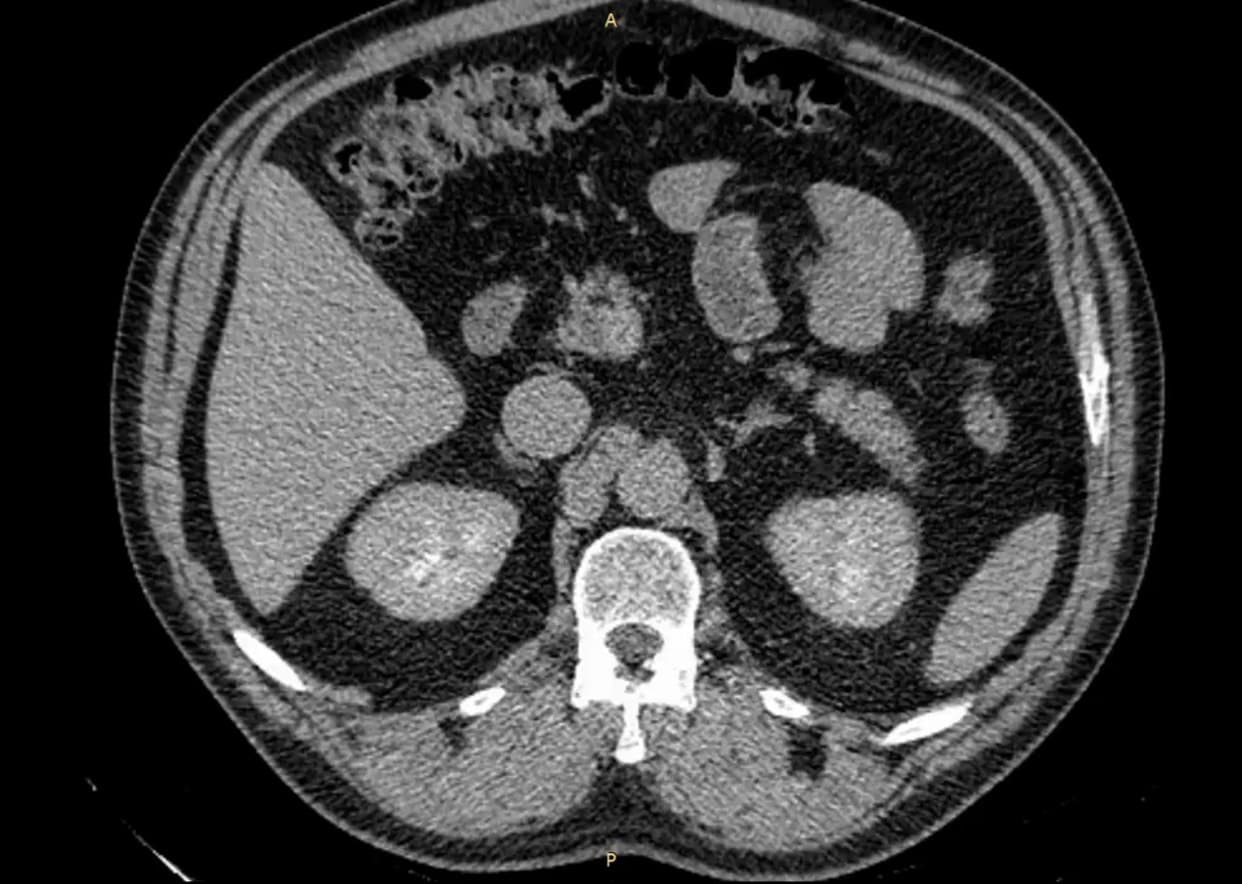

Мужчина 52 лет наблюдался в поликлинике с доброкачественным новообразованием в почке. Его беспокоили периодические боли в пояснице слева. Ранее выявленная киста почки росла, вызывая нарушение оттока мочи и угрозу снижения функции почки.

«Самое сложное — интероперационно правильно определить место, где надо рассекать. Чтобы создать сообщение. Мы изучали КТ-снимки, архитектонику почки, чтобы свести к минимуму определённые риски травмирования сосудов почки, — рассказал Владимир Новосёлов, врач-уролог, заведующий отделением урологии №2 клиники «Нефтяник, - Операция прошла в штатном режиме. После вмешательства установлен временный дренаж, через который будет происходить постепенное уменьшение размеров кисты вплоть до её полного исчезновения».